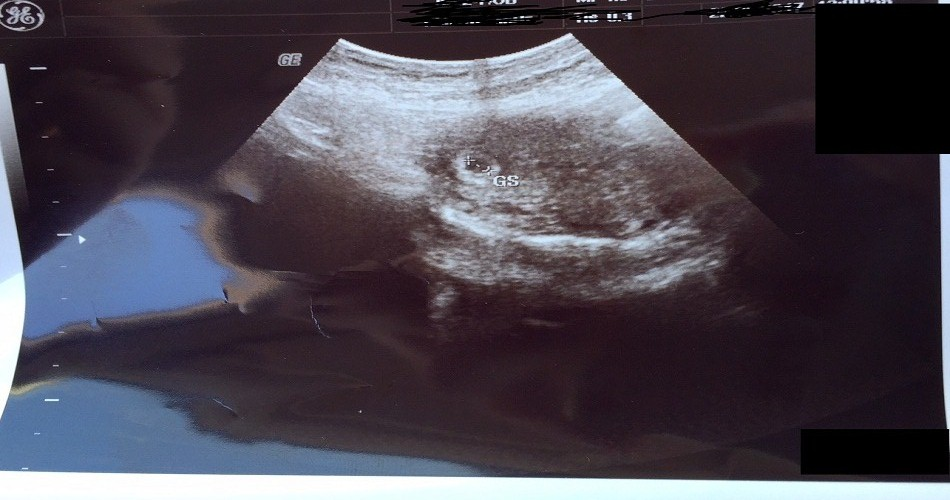

Hamilelik süreci uzun ve zor bir süreçtir. 9 ay 10 gün süren hamilelik ortalama olarak da 40 hafta sürmektedir. Hamileliğin 5. ayı ise bu zorlu sürecin yarısı olarak sayılmaktadır ve ilk aylardaki risk tamamen azalmıştır. 5. aya gelen hamilelikte bebek ilk aylara göre büyümüş ve anne tarafından hissedilmeye başlanır hale gelmiştir. Bu ay itibariyle bebeklerin elleri ve bacakları görünmeye başlamış, ultrason görüntülerinde hareketleri de net olarak görüntülenmektdir. Hamileliğin 5. ayı içerisinde kalan 17, 18, 19 ve 20. haftalarda yaşanan değişiklikleri aşağıda detaylı olarak sizlerle paylaşacağız.